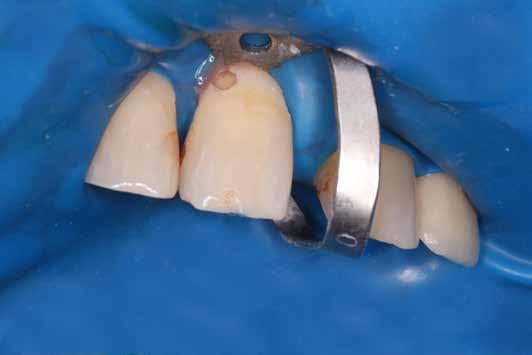

A megfelelő vizuális kontroll és az izolálhatóság kedvéért lebenyt alakítottunk [4. kép]. Így az abszolút izolálás már kivitelezhető volt és kofferdám izolálásban kezeltük a léziót [5. kép]. Mivel az elváltozás nem látható területen helyezkedett el, illetve a kavitás kis kiterjedését figyelembe véve kalcium-szilikát bázisú anyagot választottunk a restauráláshoz (Biodentine, Septodont) [6. kép]. Miután letelt a választott anyagunk kötési ideje (12 perc), zártuk a lebenyt [6. kép]. Páciensünk azóta is panaszmentes, kétéves kontrollon állapota rendben volt [7. és 8. kép].

14. kép: Kofferdam izolálás és a gyökércsatorna kiblokkolása guttapercha segítségével.

15. kép: A fog restaurálására mikro-hibrid kompozit tömőanyagot alkalmaztunk.